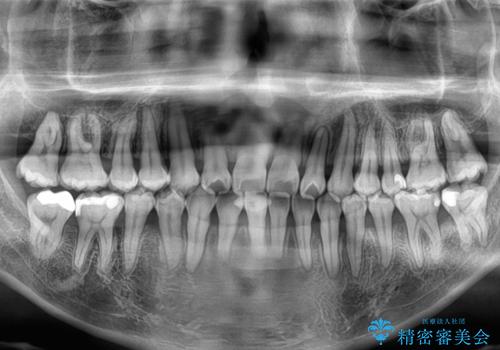

- 上下前歯部のデコボコを主訴として来院された患者様です。

上顎の歯列弓が下顎に対して狭いため、臼歯のかみ合わせがが咬頭対咬頭の状態です。

上顎の急速拡大装置を使用して、上顎骨を側方に拡大することで上顎歯列弓を拡大し、それに伴い下顎歯列弓も拡大できるようにして、歯列を整えていくこととしました。